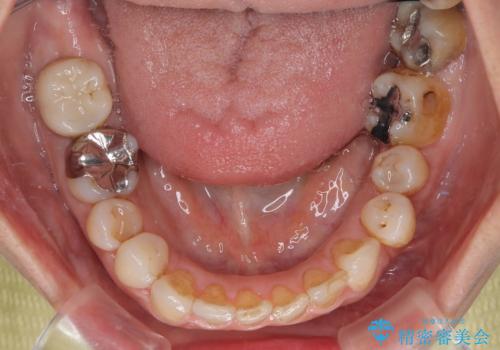

痛みがなくなり歯列が整ったことで、残っている銀歯も気になり始めているようです。

マウスピース生活に疲れてしまったとのことで、暫くお休みをしてから銀歯の治療を再開していく予定です。